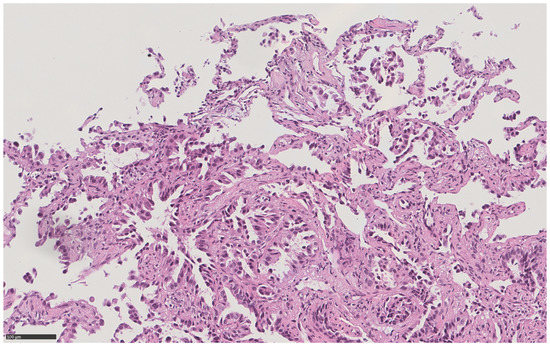

Histopathological diagnosis of lung adenocarcinoma showing lepidic, non-mucinous, and acinar patterns (Figure 2), explained the nodular radiological pattern, while the subsequent demonstration of the c.2573T > G p. (Leu858Arg) mutation in exon 21 of the EGFR gene explained the whole remaining clinical scenario: a diffuse miliary oncological disease, often characterized by rapid progression, in a non-smoker patient [4].

Figure 2. High power (21x) hematoxylin and eosin view of a bronchoscopic transbronchial pulmonary sample in the same patient, showing primary lung adenocarcinoma with lepidic non mucinous and acinar patterns.